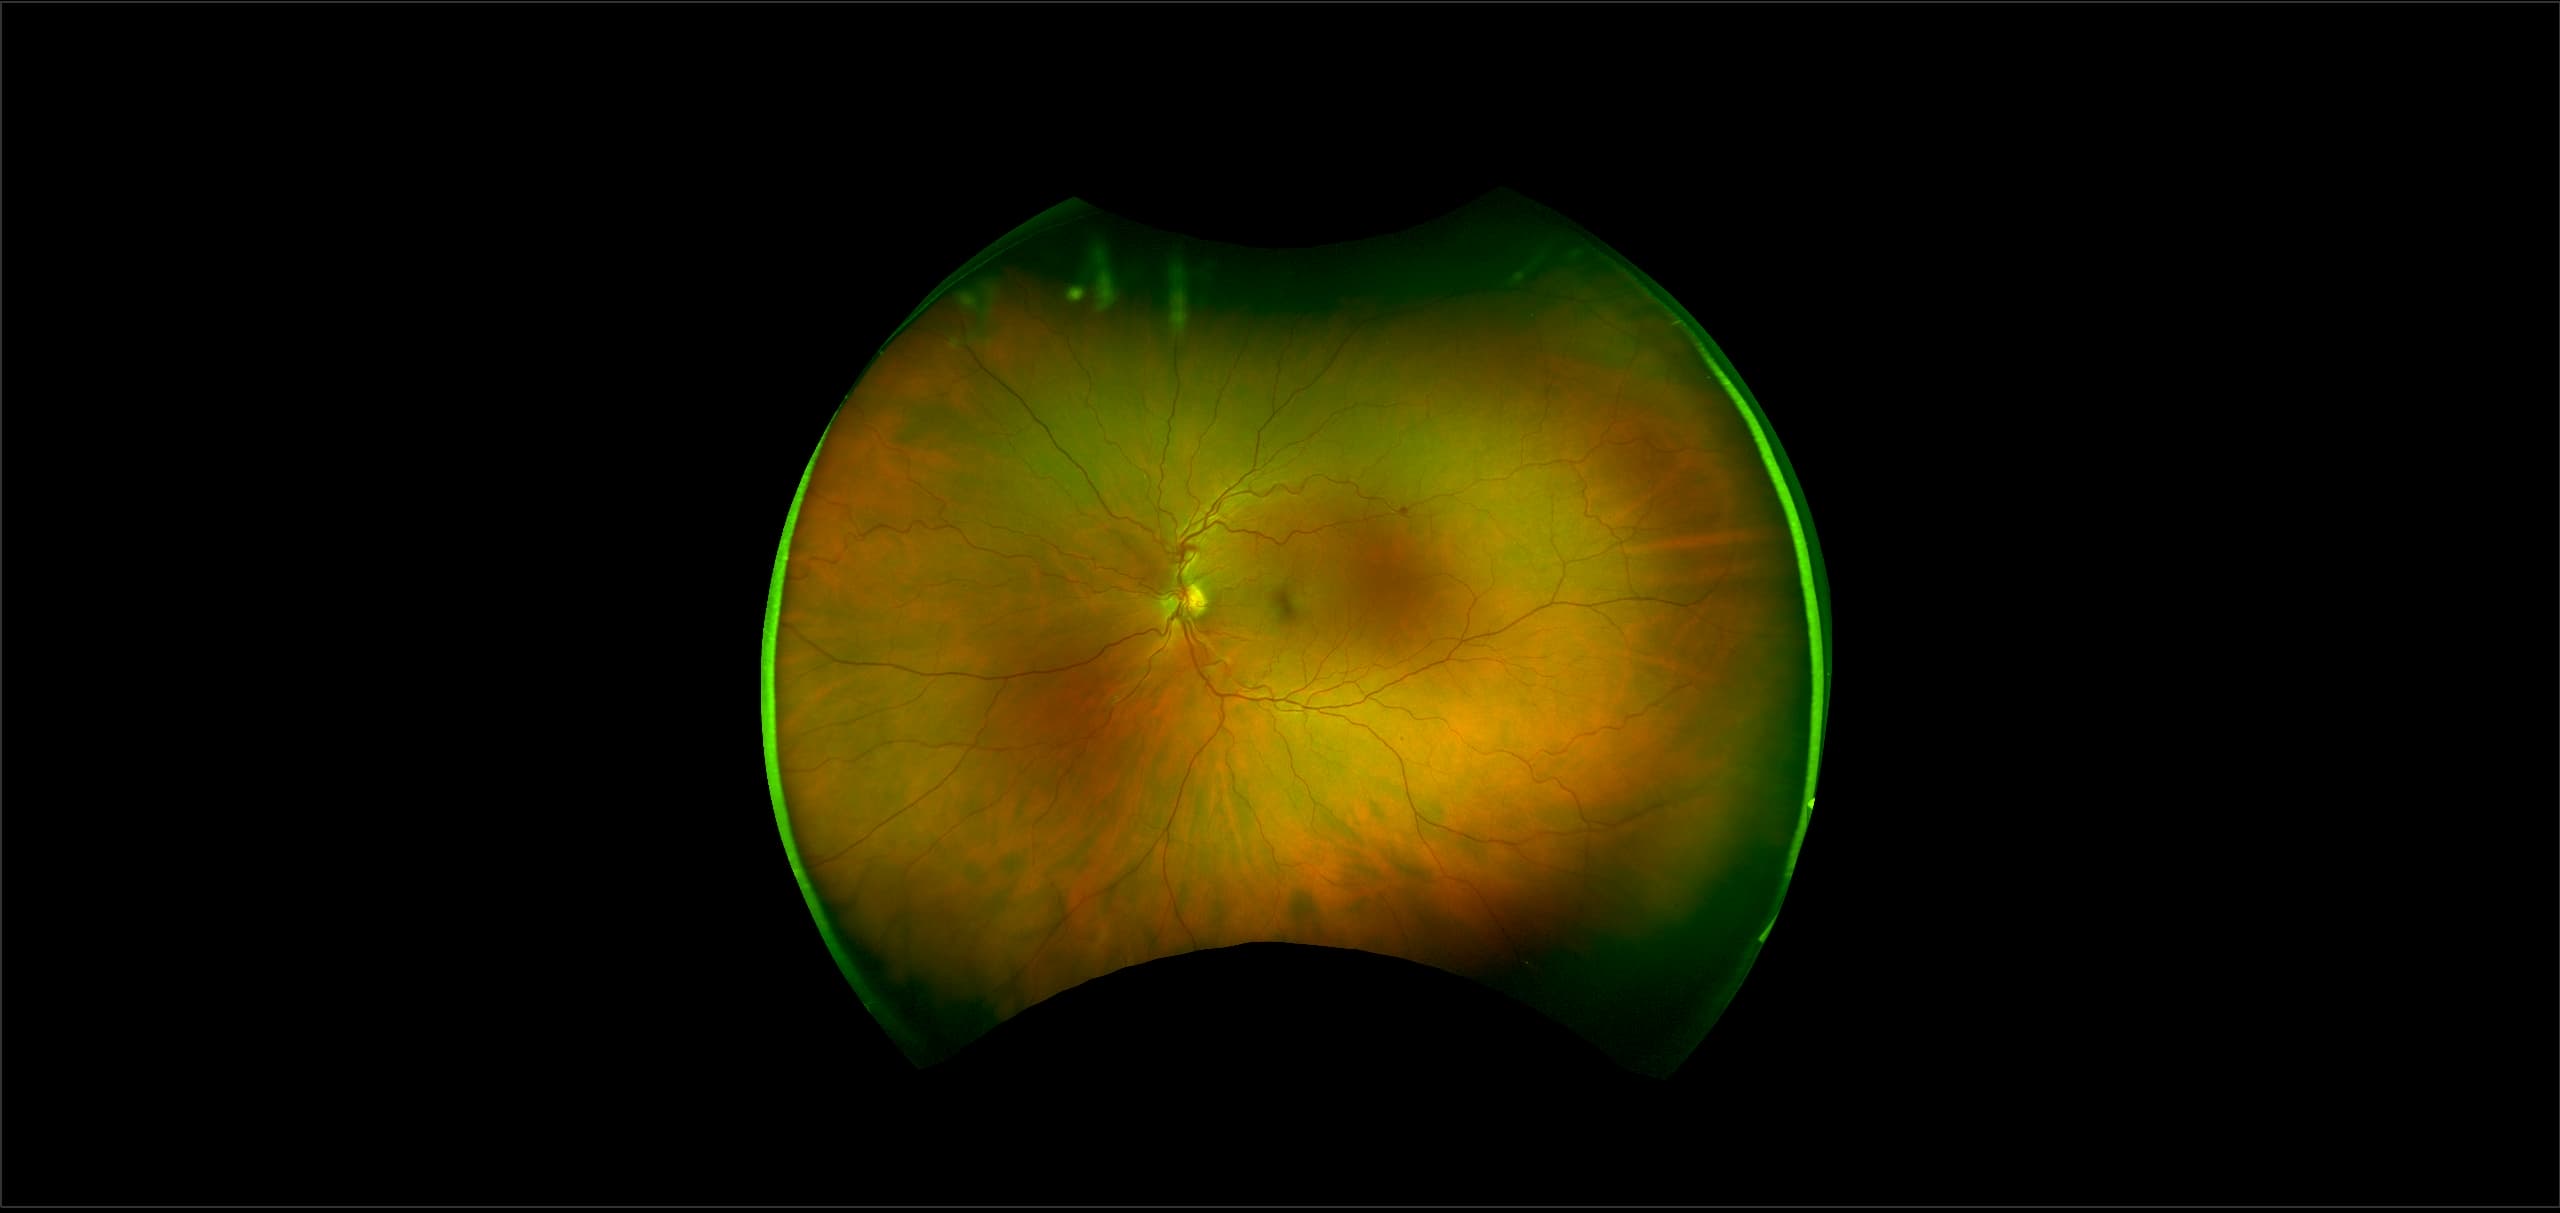

RPE hyperplasia results in a proliferation of RPE cells and thus, forms a pigmented retinal lesion which is very irregular in shape. All that is necessary is a proper stimulus to the RPE and this may be provided by physical stimulation such as vitreous traction or inflammation from infection or trauma. Sometimes a small area of this condition is called pigment clumping (gathering of RPE cells).